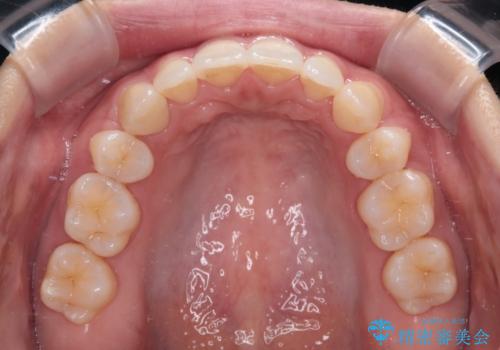

- 上下前歯の隙間と口元の出っ張った感じを気にして来院された患者様です。

上下の隙間は舌突出癖によるもので、またその癖により前歯が前方に出ている状態でした。

口元の出っ張りを改善するため、上下左右第一小臼歯4本を抜去し、ワイヤー装置にて矯正治療を行うこととしました。